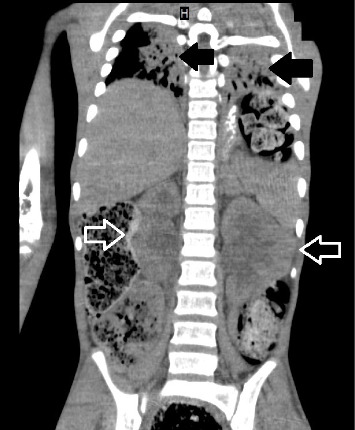

Abdominal compartment syndrome (ACS) in children is a life-threatening complication with high morbidity and mortality. Stressful life events are among the risk factors of functional constipation (FC) in children. We present a 13-year-old male patient with chronic FC due to parents' separation who presented with a history of FC since infancy and inability to defecate during the last month. On examination, the abdomen was distended and tender. His vital signs revealed elevated blood pressure ≥ 95th percentile according to his age weight and gender. On admission, the patient experienced tonic-clonic seizures refractory to medical therapy. He was intubated and a computed tomography (CT) scan revealed an extensive rectosigmoid bowel dilatation. Despite maximal medical support, his condition worsened. ACS was suspected and confirmed via intravesical measurement of intra-abdominal pressure (IAP). An urgent decompression laparotomy (DL) was performed with resection of the affected bowel. His condition improved postoperatively. This case highlights the extremely rare association between ACS and chronic FC resulting from stressful life events.